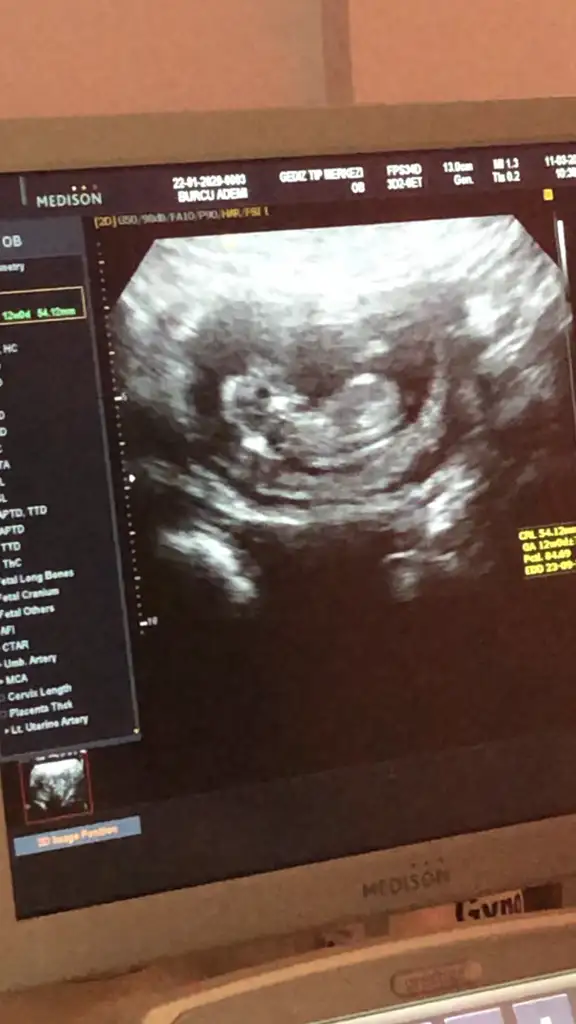

Banada bakarmısınız şimdi ikili testten çıktım doktor erken dedi soylemedi çok merak ediyorum 12 haftalik

Eklentiler

• 20200318_143521.webp

20200318_143521.webp

37,2 KB · Görüntüleme: 49